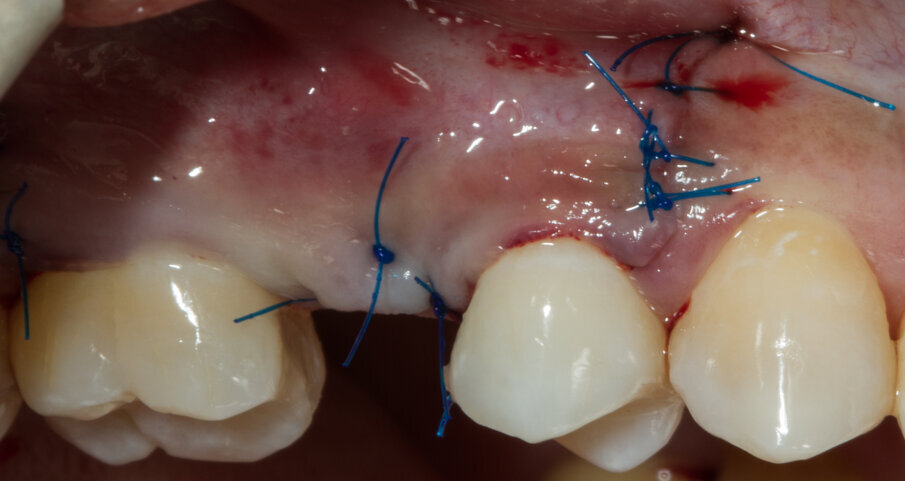

Dopo aver passivizzato il lembo si esegue una sutura a materassaio orizzontale e punto staccato centrale sulla parte crestale e suture semplici sulle incisioni di scarico (Figg. 13, 14). Dopo 10 mesi di guarigione si può procedere all’intervento di posizionamento implantare (Figg. 15-17). Sia dalle fotografie a lembo aperto (Figg. 18, 19) e da quelle di confronto tra la situazione alla baseline e dopo rigenerazione della cresta ossea (Figg. 20, 21) si può valutare come si sia ricostituito un osso ben corticalizzato, vascolarizzato, che ha riempito tutto il difetto osseo preesistente.

Fig. 13 - Sutura del lembo.

Fig. 14 - Sutura a materassaio orizzontale.